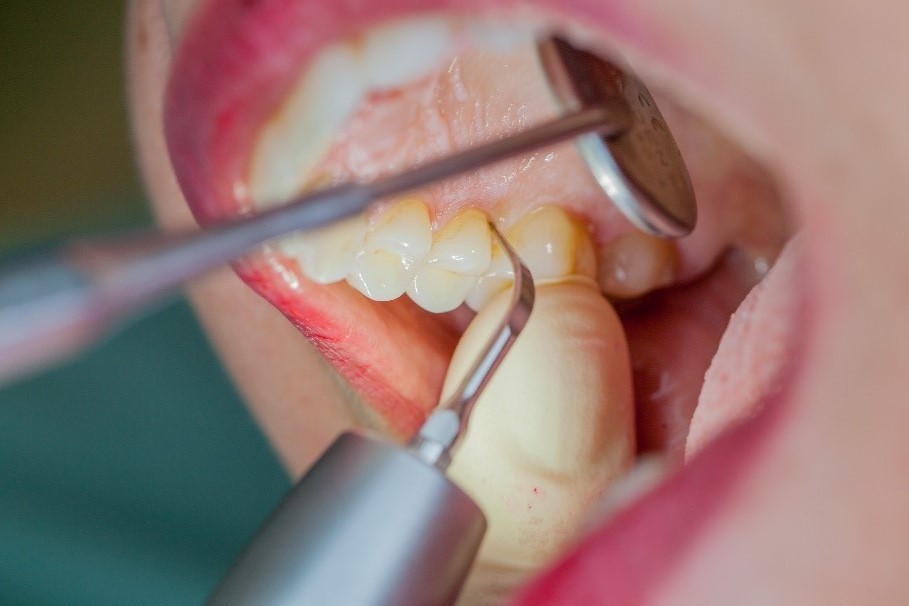

Where necessary, initial periodontal treatment is carried out. First, professional tooth cleaning establishes healthy gingival conditions. In this procedure, calculus (Fig. 1) and biofilm (Fig. 2) are removed as far as the gingival sulcus. In combination with careful instruction on oral hygiene, this gives the patient the basis for long-term freedom from inflammation.15

Calculus removal using an ultrasound

Fig. 1: Calculus removal using an ultrasound (W&H Tigon+ with a 3U tip) is a key part of professional tooth cleaning.